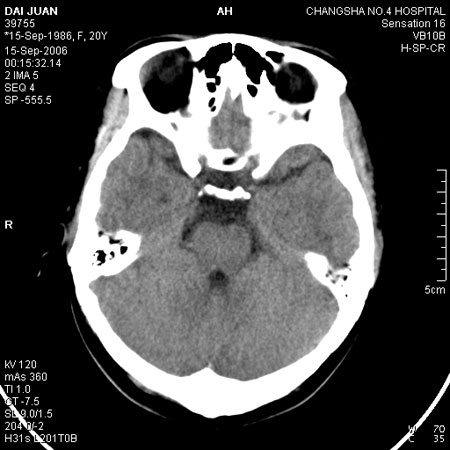

请问各位战友:图示箭头处是否为颅骨骨折?

病史:患者,女,20岁.头部及腹部外伤20分钟.伤后昏迷,无呕吐.头及右侧腰背部疼痛,双侧瞳孔等大,

右肾区叩痛.其它无异常.患者家属否认原有外伤史.

请大家看看是否为颅骨骨折.还是正常变异,或为陈旧骨折.谢谢.

图片未上传完,所见图象示枕骨线样低密度影,边缘锐利,结合外伤史,伤后昏迷,骨折不能除外。

枕骨的线样低密度影锐利、清晰,但正好位于矢状缝的位置,局部无明显软组织肿块,相临及对冲部位脑实质亦无出血及挫裂伤表现。

单就这几层暂不考虑骨折,建议上传完整图片。

枕部锐利透亮线,可以考虑枕骨骨折.

枕骨是单块的,矢状缝是在顶骨而不是在枕骨,枕骨后缘见线状低密度,边缘税利,考虑在骨折存在。

枕后部及左侧颞枕部边缘锐利的线样低密度影,局部软组织无异常,左侧乳突蜂房密度均匀,硬膜下及脑实质内未见出血灶,考虑为正常变异。

枕部锐利透亮线,可以考虑枕骨骨折.左侧枕颞缝。

枕部考虑骨折。一般的颅逢不会跨越板障,楼主所示枕骨断面两侧板障也不连续。

ct 扫描发现枕骨变异一例

患者男,19 岁。因头部外伤就诊。体检:营养、发育良好,五官对称,外观无畸形。右额部见局部皮肤青紫,无皮肤破损。ct 扫描:脑组织及颅外软组织未见异常;骨窗见枕骨中下部,由枕骨内、外隆凸至枕骨大孔处有一线样长约27 mm裂隙(图1、2),宽约1 .0 mm。边缘光滑、硬化,贯穿枕骨内外板。颅骨无

凹陷及移位征象。

讨论: 胚胎学研究证实,枕骨发源于脊椎而不是颅骨,在胚胎形成40 ~ 42 体节时,前部5 个体节形成

枕骨。枕骨基底部和鳞部各有一个骨化中心,还有两个枕骨外侧部[1],分别出现于胚胎的第7 周及第8 周。本例枕骨枕鳞部骨缝可能与枕骨各骨化中心发育障碍有关。经枕骨隆凸至枕大孔处骨缝变异极为罕见,易误诊为骨折,细致观察骨缝边缘是否有硬化和软组织是否肿胀即可与骨折相鉴别。